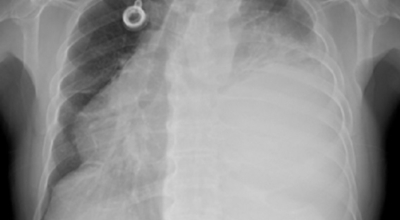

폐암이란

폐암은 폐에 생긴 악성 종양입니다. 폐 자체에 나타나는 원발성 폐암과 다른 장기에서 전이되어 온 전이성 폐암이 있습니다. 전 세계적으로 해마다 130만 명이나 되는 사람들이 폐암으로 사망하는데 이는 암에 의하여 사망하는 것 중에 가장 높은 비중을 차지하고 있습니다.